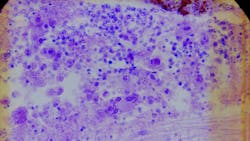

The funding, which will support the project "Assessment of a Novel Methodology for Endpoints Assessing Response to Lymphoma Treatment in Real-World Studies," will evaluate the accuracy of real-world data (RWD) for lymphoma tumor response compared to blinded independent central review, the gold standard in randomized clinical trials. Within this research, Cardinal Health will work with the FDA Oncology Center of Excellence to assess tumor response in the clinical care setting.